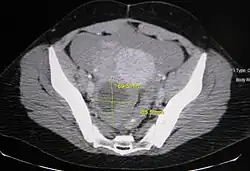

Diagnosis

Ovarian cysts are usually diagnosed by pelvic ultrasound, CT scan, or MRI, and correlated with clinical presentation and endocrinologic tests as appropriate.[15] Ultrasound is the most important imaging modality, as abnormalities seen in a CT scan sometimes prove to be normal in ultrasound.[5][8] If a different modality is needed, then MRIs are more reliable than CT scans.[5]